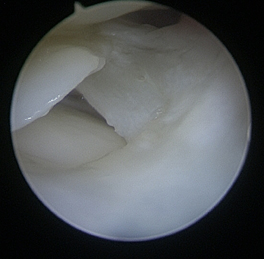

Le débridement consiste à régulariser les lésions centrales à l’aide de rasoirs à lames rotatives que l’on appelle « shaver ». Ce traitement est indiqué pour les lésions centrales dégénératives ou traumatiques.